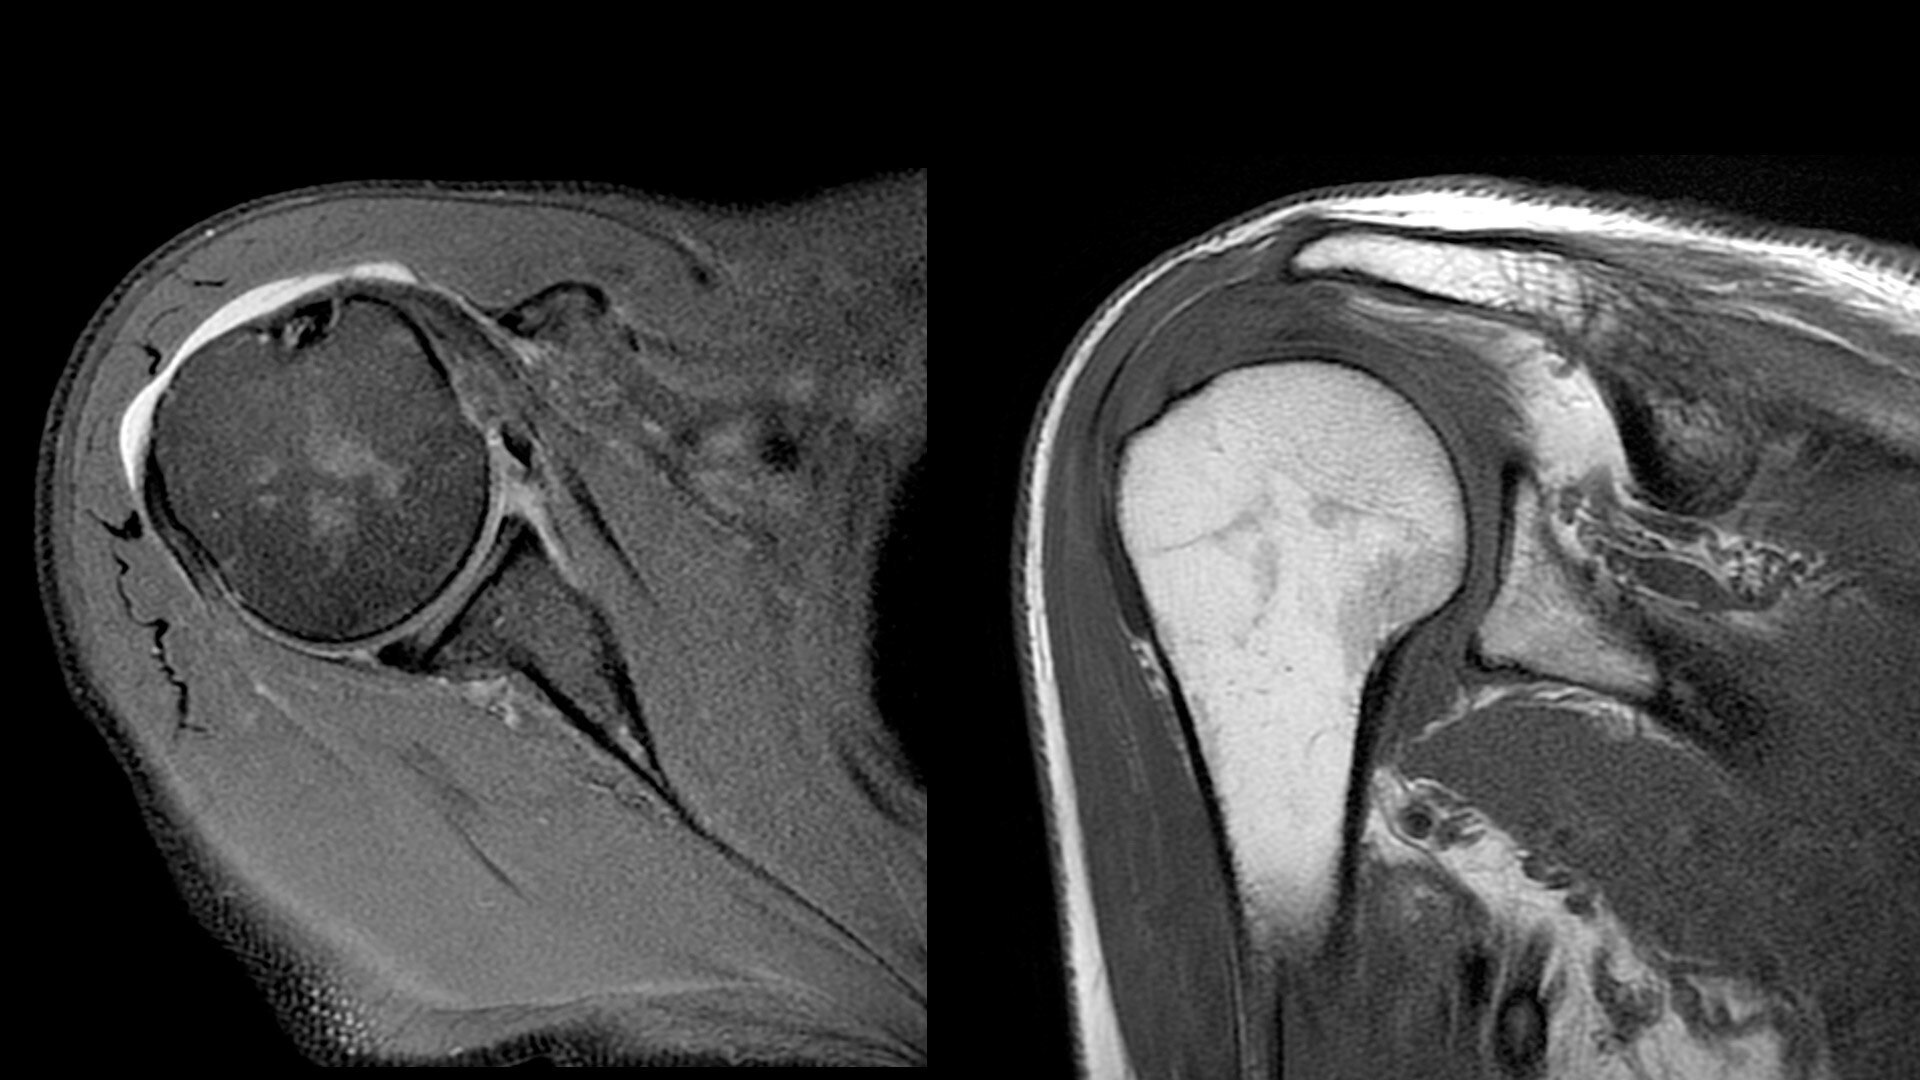

The shape of the MRI coil no longer determines what you can do with it. Wrap it around a knee for a complete knee image. Drape it over the patient's body. With an adaptive AIR™ Coil that is light, form fitting and easy to position, it’s the closest you can get to total positioning freedom with 360-degree coverage.

• 360 degrees of coverage for MSK imaging

• Positioning freedom with previously hard-to-scan anatomies

• 20-ch and 21-ch design to accommodate all patient sizes and anatomies